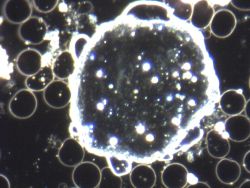

Die Dunkelfeldmikroskopie ist ein besonderes Verfahren der Blutanalyse, das Anfang des 20. Jahrhunderts von Prof. Dr. Günther Enderlein entwickelt wurde. Anders als bei der klassischen Lichtmikroskopie wird das Blut dabei seitlich beleuchtet. So erscheinen Zellen und Strukturen vor einem dunklen Hintergrund in hoher Kontrastschärfe.

Ein Tropfen Kapillarblut aus Fingerbeere oder Ohrläppchen reicht aus, um ihn sofort unter dem Mikroskop sichtbar zu machen. Durch die Beobachtung „in Echtzeit“ können nicht nur Form und Anzahl der Blutzellen betrachtet werden, sondern auch ihre Beweglichkeit, Vitalität und ihr Zusammenspiel. Zusätzlich lassen sich bestimmte Strukturen erkennen, die Hinweise auf das innere Milieu geben können.

Besonders interessant: Das Blut verändert sich über die Zeit. Daher wird es nicht nur im frischen Zustand, sondern auch über mehrere Stunden beobachtet. Auf diese Weise entsteht ein dynamisches Bild, das Aufschluss über Stabilität und Veränderungen des inneren Gleichgewichts geben kann.

Die Dunkelfeld-Diagnostik versteht sich dabei nicht als Ersatz, sondern als Ergänzung zu schulmedizinischen Laborwerten. Sie bietet visuelle Eindrücke, die das Gespräch zwischen Uns und dem Patienten bereichern und ein besseres Verständnis für mögliche Belastungen oder Zusammenhänge schaffen können.